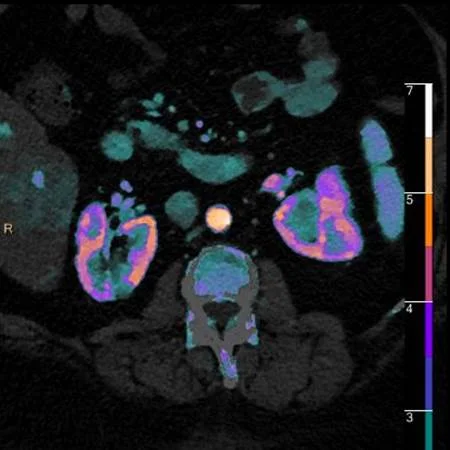

Iodine map: So easy!

Lesion nicely depicted on iodine overlay

Iodine map: The cortical defect is so easy to find!

Nicely depicted on iodine overlay.